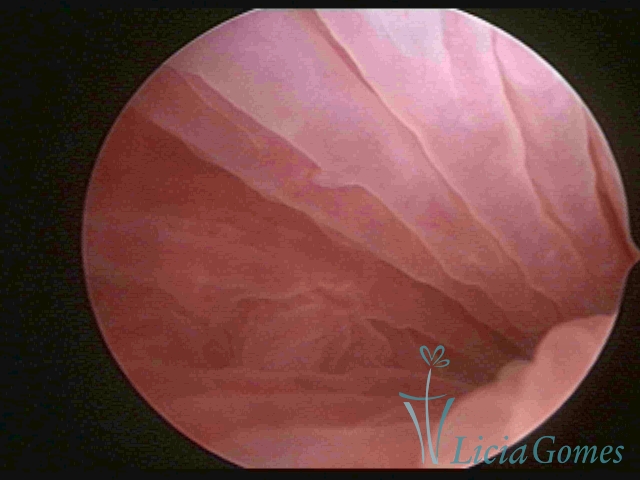

Primeira porção ou setor proximal ou setor inferior:

Durante a fase proliferativa, encontramos muco claro e cristalino pouco aderente à óptica. As criptas e as papilas apresentam-se um pouco edemaciadas e vascularizadas, micro vesicular, lembrando cachos de uva.